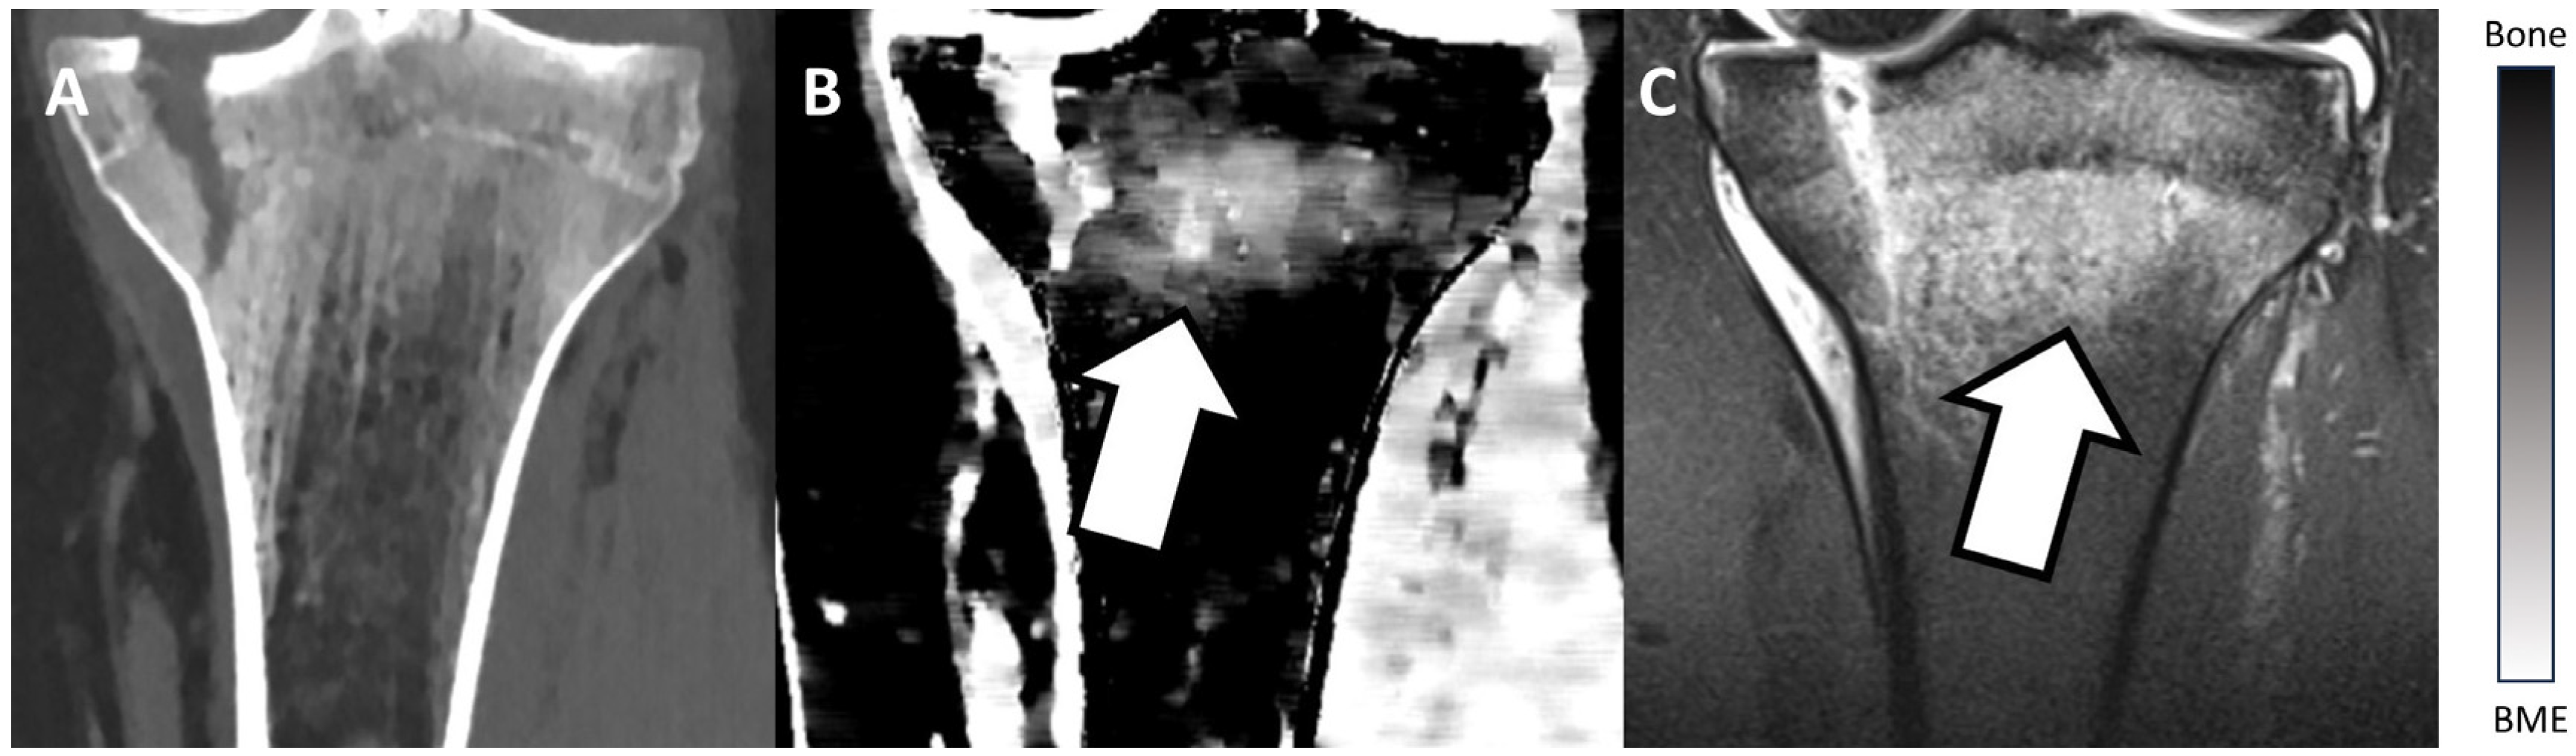

Figure 2 and Figure 3 show examples of BME on TMD images in different locations. Figure 2 presents an example of a fractured proximal tibia on conventional CT images and the TMD tool, whereas Figure 3 shows a fractured distal radius.

Figure 2.

Fractured proximal tibia of a patient on a conventional CT image (A), on the TMD tool (B), and the corresponding MRI (C). The BME (white arrow) is visible on the TMD tool and the corresponding MRI, but it is not detectable on the conventional CT image. Additionally, a bar chart shows the density/intensity levels between normal bone and BME.